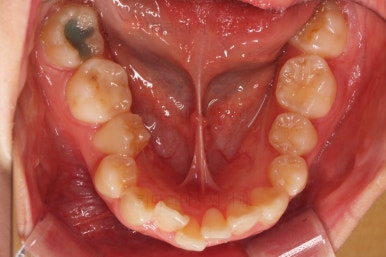

부산무턱교정치과 초진 시 입안의 모습입니다.

전반적으로 치열이 삐뚤고요. 아랫니가 윗니보다 뒤쪽으로 많이 가려져 있죠.

그래서 앞에서 봤을 때 아래 앞니가 거의 보이지 않는 상태인데요.

이런 교합을 "과개교합"이라고 표현합니다.

전반적인 교합, 치열, 과개교합, 튀어나와 보이는 앞니 등을 개선해줘야겠네요.